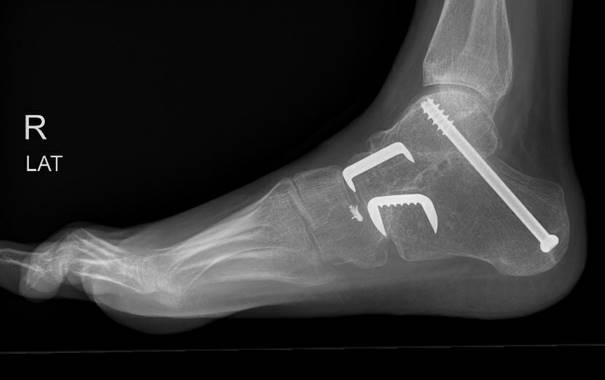

De operatie

Er worden meestal drie incisies gemaakt: één aan de buitenkant, één aan de binnenkant van de voet en één onder de hiel. Hierna wordt het kraakbeen van het onderste sprong- en middenvoetsgewricht geheel verwijderd. De botten worden met meerdere schroeven en eventueel één of meerdere krammen in de juiste positie vastgezet. De huid wordt meestal gesloten met hechtingen die vanzelf oplossen.

Voorbeeld van een röntgenfoto na de operatie